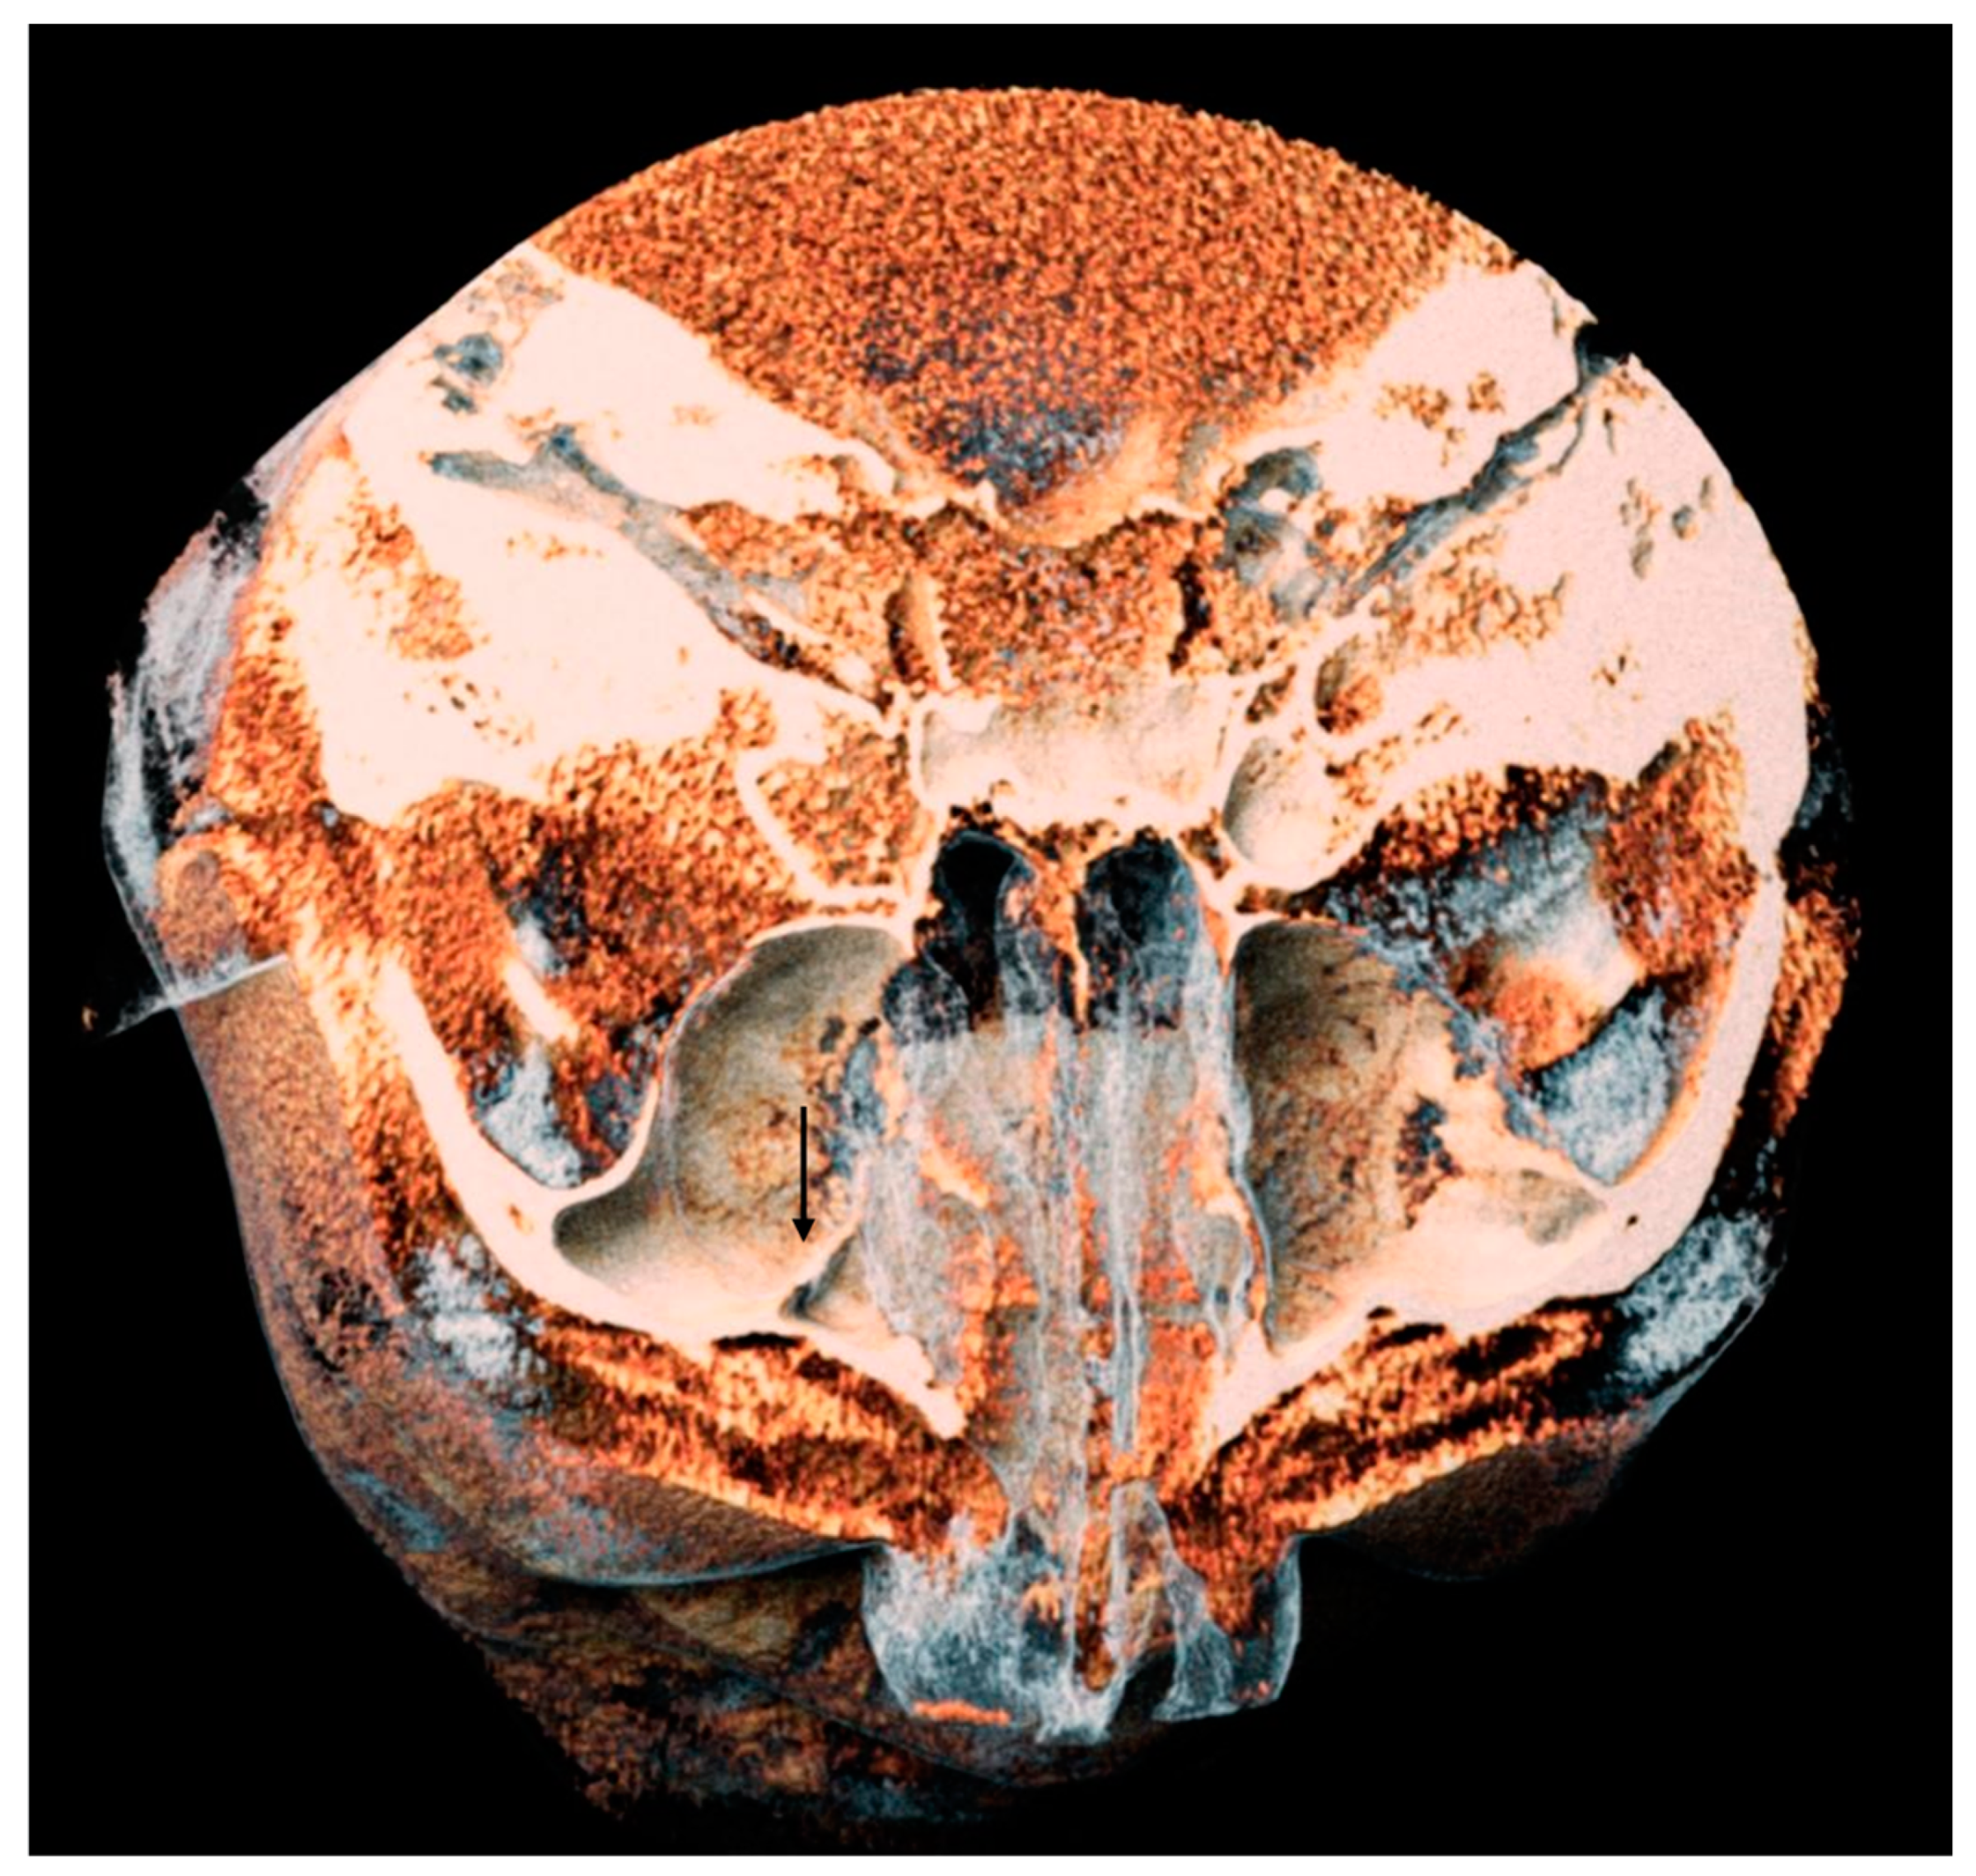

- The presence of the septa on cross-section (Figure 4);

- The height of the septa on cross-section setting from 2 mm to 0 mm, to better evaluate the maxillary sinus: this was measured from the apex of the septa to its bottom on the basal bone;

- The localization of the septa on cross-section;

- The orientation of the septa.